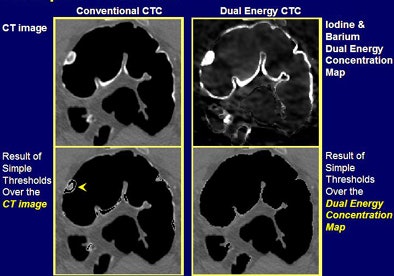

| Above, polypoid residual fecal material (15 mm) was left in place by the conventional electronic cleansing algorithm (upper left) but removed by the dual-energy algorithm (upper right). Dual-energy mapping with electronic cleansing also enabled better segmentation and identification of the descending colon. In the axial view (below) of the same case, images at left depict conventional CTC with simple thresholds applied. Images at right show the iodine and barium dual-concentration map with the electronic cleansing thresholds applied. |